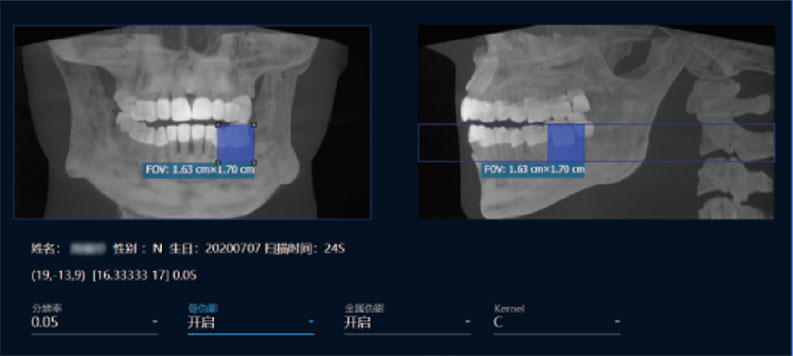

采用高性能CMOS探测器,最大FOV可达16x9cm星垂视野并支持无极可调,最小体素0.05mm。头颅采集模式,支持3s超快速扫描,最小像素99um,保证优质影像快速采集。

局部超清显示、 移动视野摄片

真人正侧位投影,实现CT成像区域无极可调

可根据临床需求任意调整成像区域大小实现局部超清三维显示